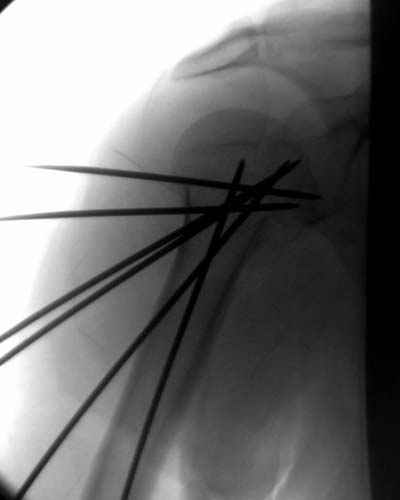

Женя, а как ты водишь спицы, в смысле, как делаешь входное отверстие, и как в него проводишь V-спицу? А то о дна из спиц, та, у которой не дошла до головки одна палочка буквы V, как-то выглядит на рентгенограмме, как будто или через очень большое отверстие введена, или каждая половинка через отдельные отверстия.

Спицы провожу по передней и задней поверхностям плечевой кости через 4,5 мм отверстия на разных уровнях.

Уточни - обе части буквы V вводишь в одно отверстие? А то по снимкам выглядит, что в разные.

V-спица проводится через 4,5 мм отверстие. Видимо, из-за разной длины вторая половина спицы *пролетела* мимо отверстия, что и привело к вторичному смещению костных фрагментов.